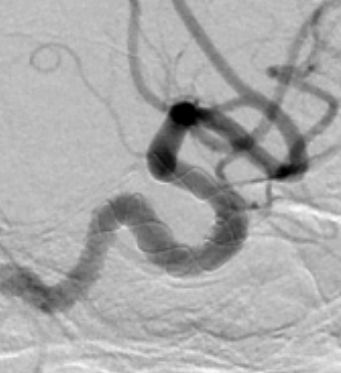

入院后行全脑血管造影证实右侧颈内动脉眼段动脉瘤。瘤颈宽约4.91mm,瘤体最大径约8.21mm,载瘤动脉远近端血管直径分别为3.07mm、3.52mm。

正侧位造影示动脉瘤内造影剂明显滞留,载瘤动脉通畅,血流导向作用显著。